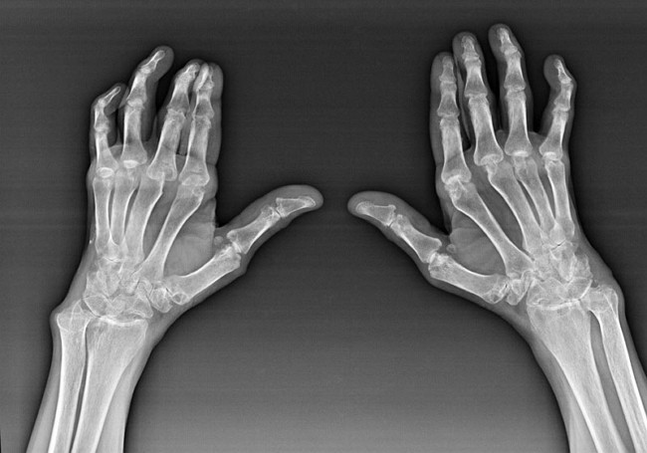

Reumatoidni artritis

Reumatoidni artritis je bolest u kojoj ljudski imunološki sustav oštećuje vlastita tkiva tijela. Drugim riječima, reumatoidni artritis je autoimuna patologija. Ova je bolest također sistemska, jer su s njom pogođena mnoga tkiva (Mišići, zglobovi, plovila itd.) i organi (Srce, bubrezi, pluća itd.) u tijelu.

Unatoč činjenici da je reumatoidni artritis sistemska bolest, u većoj mjeri, zglobovi trpe, dok je lezija drugih tkiva i organa u pozadini. S ovom bolešću mogu utjecati na gotovo sve vrste zglobova četkica (Zglobovi, karpalne staze, Metacarpal-Fhalanx, međufalanski zglobovi). Lezija je obično simetrična (oni. Pogođeni su isti zglobovi) s obje ruke, praćena oticanjem, bolovima u oštećenim zglobovima. Ujutro, tijekom dizanja iz kreveta, u pogođenim zglobovima ima neke krutosti, koji mogu trajati oko 1 sat, a zatim nestati bez traga.

Često s reumatskim artritisom u blizini pogođenih zglobova četkice (češće glasovir-falanga, međufalanga) Pojavljuju se reumatoidni čvorovi. Oni su zaobljena formacija koja se nalazi ispod kože. Na četku, ove formacije se najčešće pojavljuju na leđima. Na palpaciji su gusti, neaktivni, bezbolni. Broj njih može varirati.